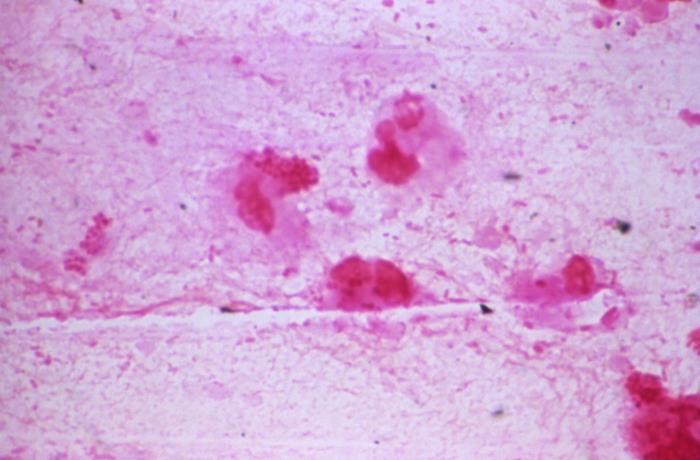

COVID-19

COVID-19 is the most recent vaccine on the list and the most politically charged. Health officials also removed it from universal recommendations first, back in October 2025, before they announced the broader changes to the schedule in January. The virus that causes COVID-19, SARS-CoV-2, continues to circulate and mutate. Children generally fare better than adults. But severe illness and death do occur, and some children develop long-term symptoms after infection. The vaccine was added to the childhood schedule in late 2022. With the goal of reducing both individual illness and community transmission.

Uptake was never high. By 2023, fewer than 10% of eligible children had received the vaccine, making it an outlier on the schedule. Federal officials cited this low uptake as one reason for removing the universal recommendation, and because healthy children face a lower risk from the virus than other age groups. The vaccine remains available through shared clinical decision-making. Parents who want it for their children can still get it at no cost. What has changed is that the federal government no longer recommends it for every child.